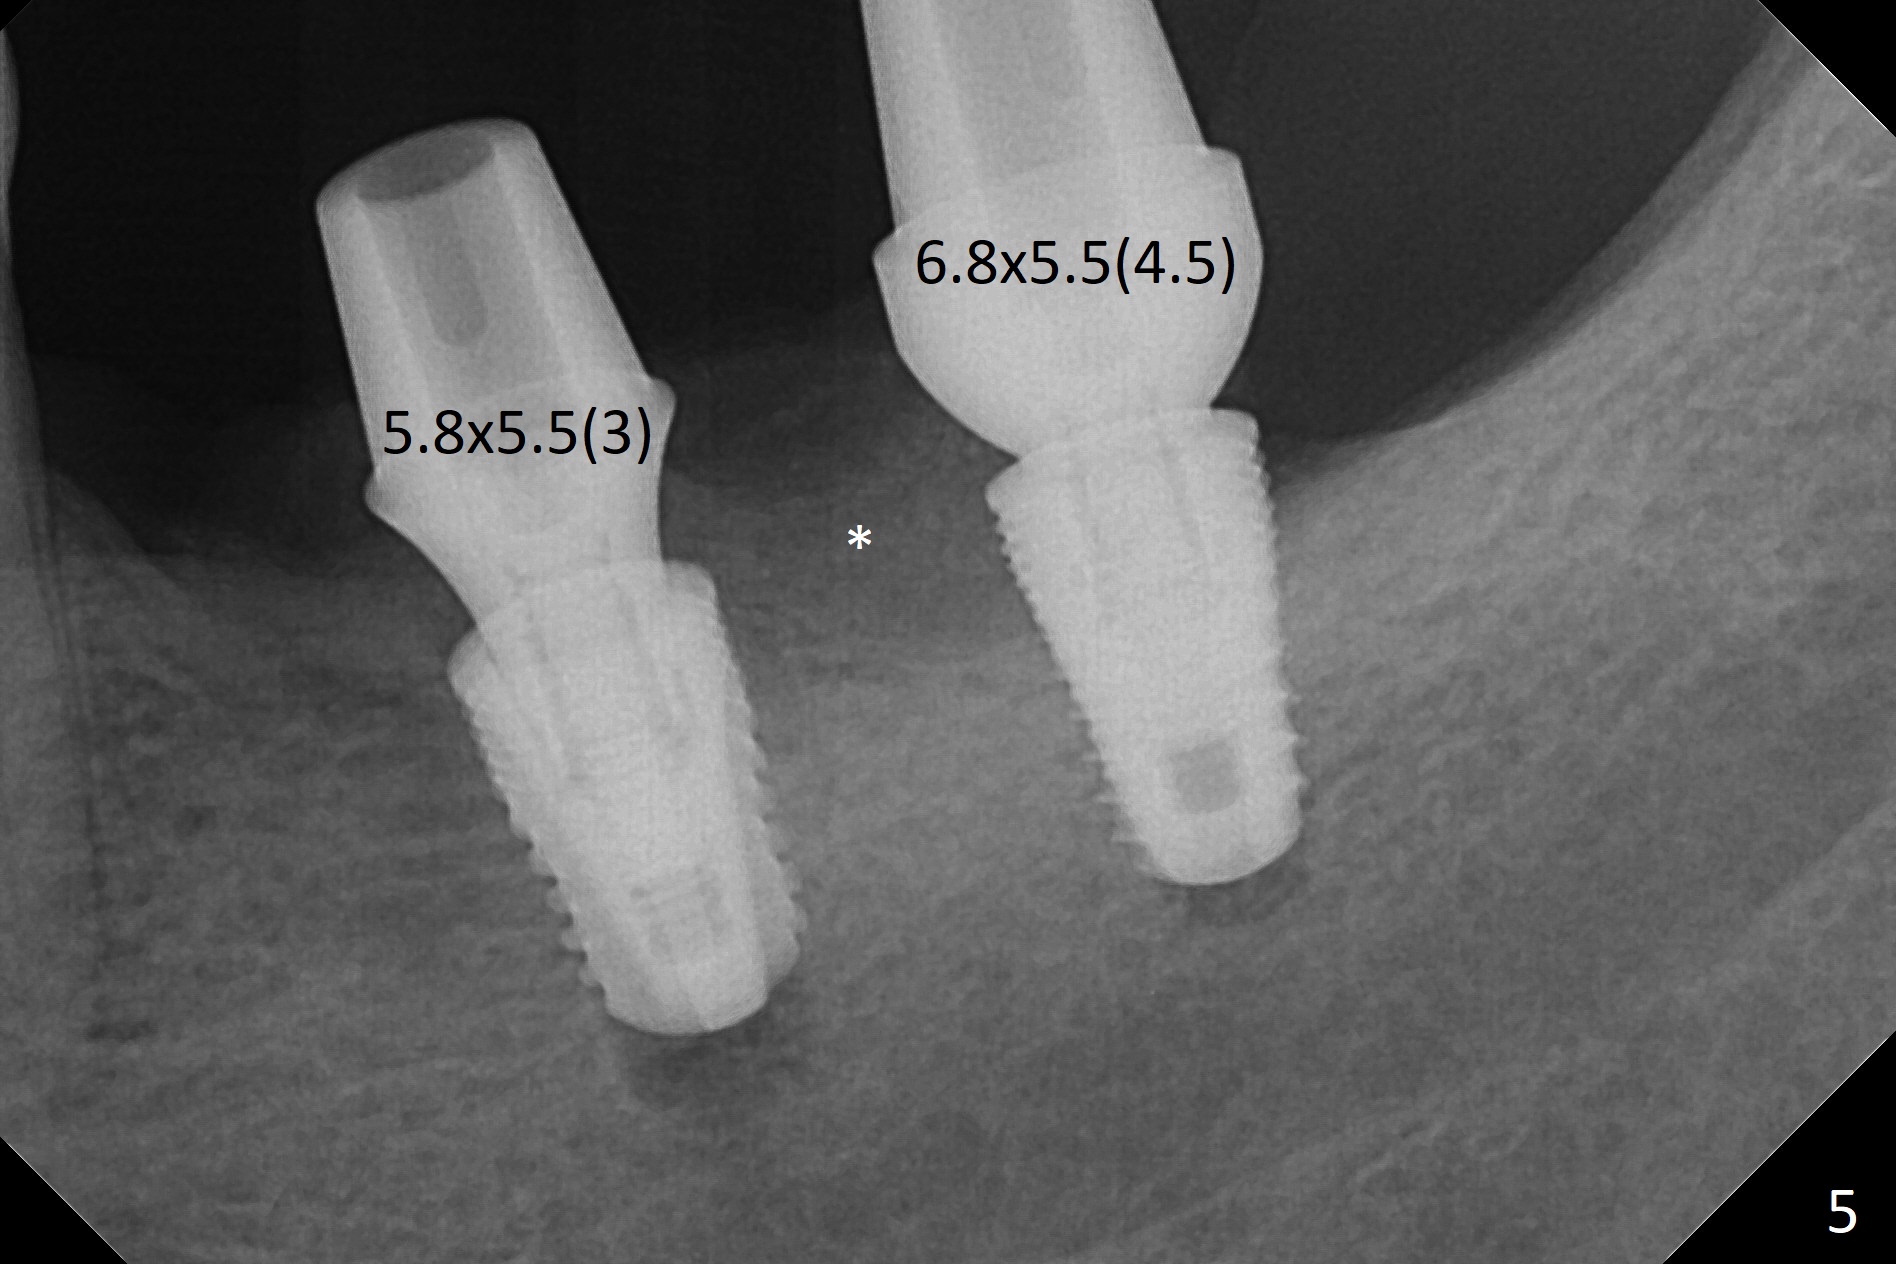

Preop photo shows severe mesial tilt of the tooth #18 (Fig.1). After extraction, the osteotomy is established in the apical end of the socket, where the buccolingual width is limited. It appears that an extra wide implant (5.9 mm) may perforate one of buccolingual plates. On the other hand, the buccal plate (Fig.2 double arrows) is intact and approximately 2 mm tall, whereas the lingual one is thin and lower. Initial osteotomy confirms that bone heights at #18 and 19 are 6 and 8 mm, respectively. Counting 2 mm of the buccal plate and bone graft lingually, a 8 mm long implant may be a practical option at the site of #18. After initial placement of two of 5x8 mm SM implants (Fig.3), the depth of the implant at #19 is adjusted twice (Fig.4,5). With placement of autogenous and allograft (Vanilla, Fig.5 *)) and abutments, a piece of cotton pellet is placed in each abutment well (access, Fig.6 *). Periodontal dressing is applied to the abutment wells for additional retention (Fig.7 *). Due to local poor oral hygiene, splinted provisional is fabricated 4 months postop (Fig.8) in preparation for limited orthodontic uprighting the tooth #20. The patient has pain with mastication at #18 eleven months post cementation (Fig.9). It appears that both of the implants should be removed with immediate replacement and bone graft. Prepare 4 PRF and sticky bone. The new implant will be 5.0 or 5.5x5 mm (Fig.10 green) with 2.3 mm platform (white). A block graft will be harvested from the ipsilateral ramus using 9/8 and 6/5 mm trephine burs for 2-3 mm in depth (Fig.11 blue). The ring graft will be seated around the platform over the implant (Fig.12).